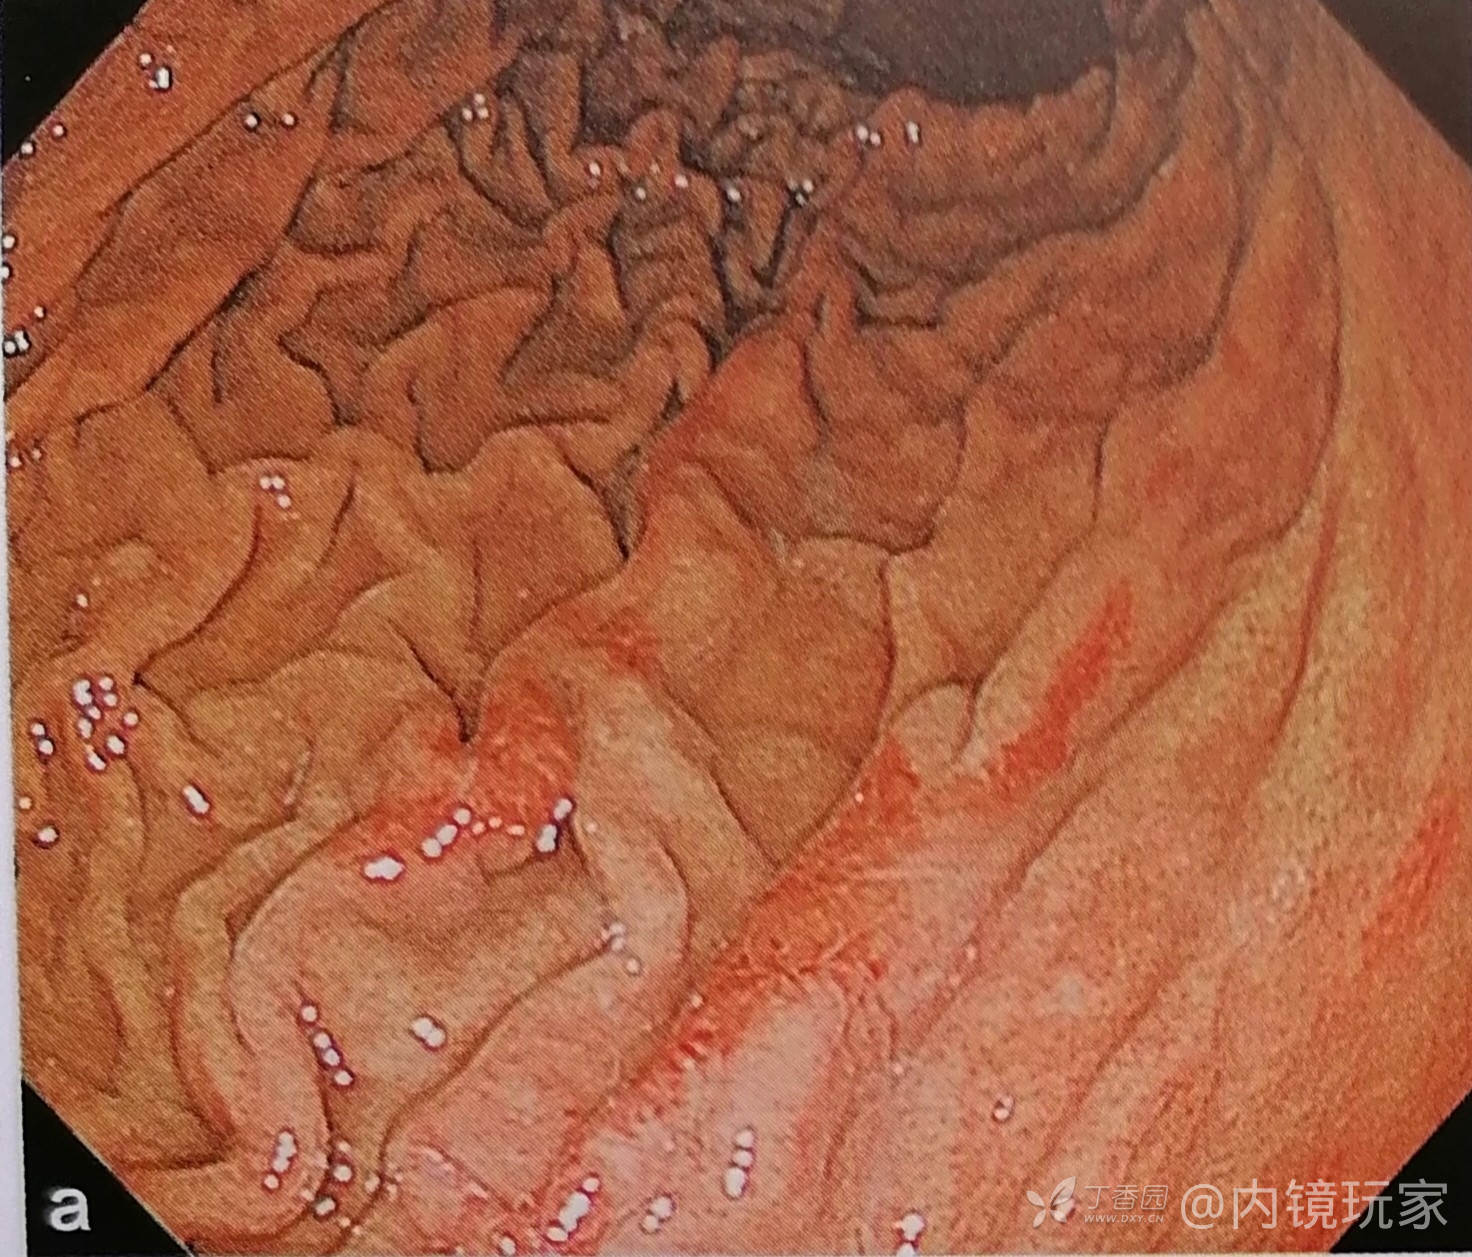

12.脊状发红(带状发红)

延胃长轴方向走形的带状发红,数条大致平行,多见于皱壁顶上,可伴糜烂。

(可见于正常胃、抗HP后、胆汁反流刺激等,重者可致腹痛。)